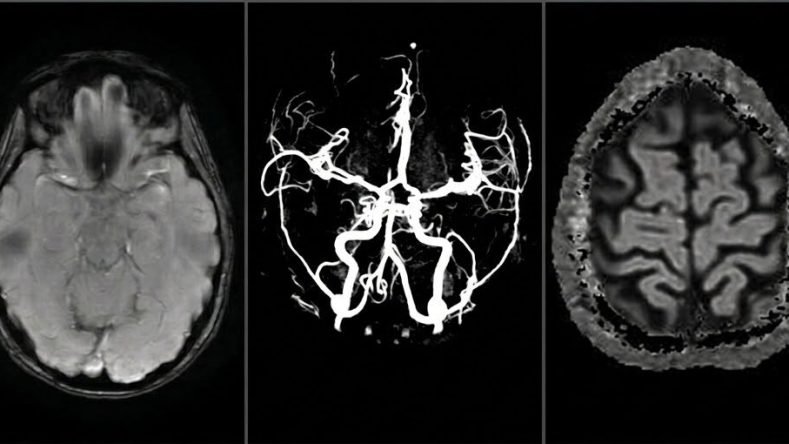

Estoy en una capilla pequeñísima que hace algunos días descubrí a diez cuadras de mi casa. Está un poco escondida, detrás de una casona antigua, rodeada de árboles. Un cura habla mientras mira a las cinco o seis personas que hay alrededor. Habla de la resurrección, de la oscuridad que fue necesaria para que Cristo viera la luz. Escucho algunas palabras sueltas, estoy aturdida. Me laten las sienes. Solo pienso en las imágenes de mi cerebro que hace algunas horas la clínica me envió por mail: inconexas, oscuras, asimétricas. Hay agujeros, vacíos, puntos. Las de vasos intracraneales se parecen el póster de la peli de Donnie Darko. Vuelvo al cura. Su cara es amable. ¿Por qué estoy ahí? Afuera llueve. No sabía que era la hora de misa. Solo sé que me llevó el dolor. Tal vez ese fue el vehículo, pero en este tiempo que ofrece espiritualidad multiplicada por decenas de experiencias, yo había quedado desconectada: absoluta y terroríficamente terrenal, llana, atada a lo diario y lo mecánico. Volví entonces al único lugar donde la paz está conmigo: donde Antonia, mi abuela, me apretaba la mano con la suya llena de anillos. Porque también eso quería decir un domingo de cruzar la plaza llena de árboles, de compras en el super, de cocinar juntas, de verla sonreír.

Lo desopilante del diagnóstico de la migraña es la ausencia. Si la resonancia está bien, si la neuróloga dice sistema nervioso, venas y arterias impecables: tenés un estatus migrañoso. Entonces tenés una enfermedad neurológica discapacitante, invisible e incurable. Solo tratable. Feroz y tétrica.